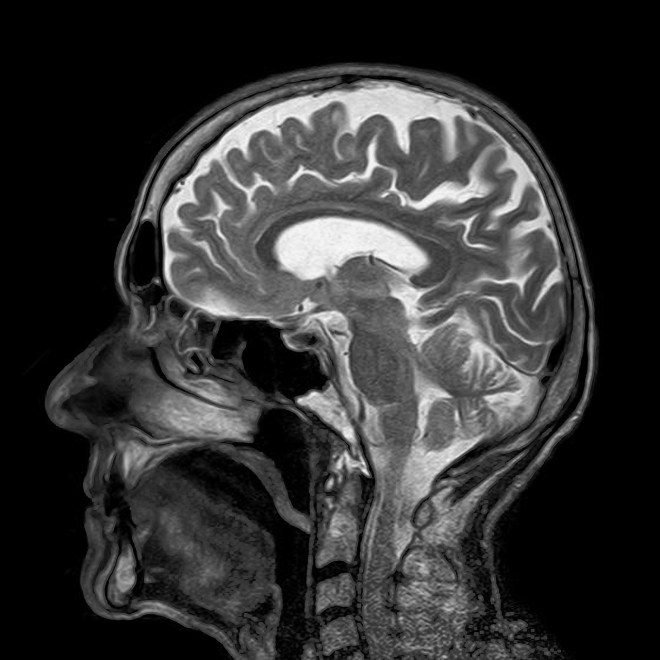

These drugs all work in the brain to control appetite and increase satiety, the feeling of fullness. The long term solution to preventing and reversing obesity may lie in finding new ways to control the processes in the brain that control eating behavior. Much of obesity management research is directed to this area.